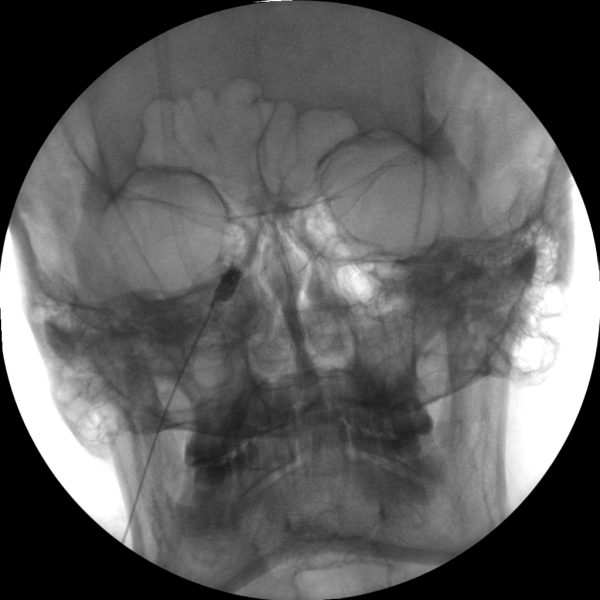

Nerve Blocks

Skan-C is an excellent choice for performing nerve blocks, a procedure that involves injecting anesthetic or anti-inflammatory medication near specific nerves to alleviate pain.